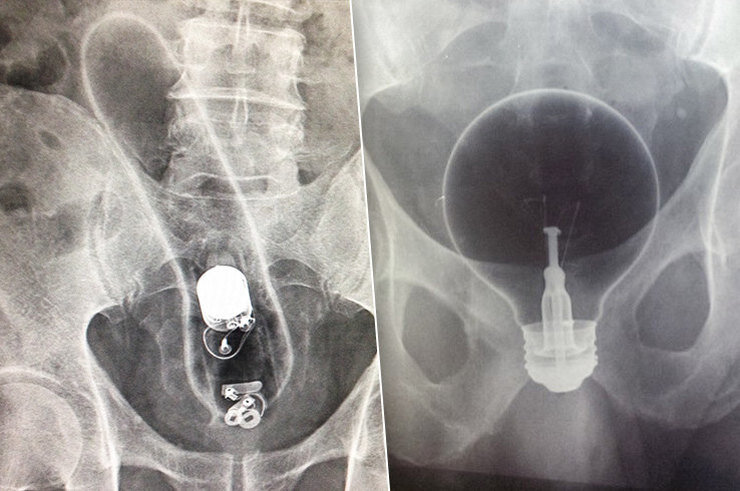

Помнишь старую шутку про лампочку, которую можно засунуть в рот, а вот вытащить — уже нет? Так вот, с некоторыми местами и предметами работает то же правило. И если тебе кажется, что речь сейчас о секс-игрушках, то ты ошибаешься. Ты даже не представляешь себе, что пытаются засунуть в себя люди. А потом не могут вытащить. Читать далее...